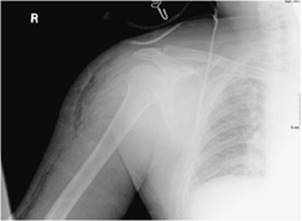

c. Type III (gas gangrene/clostridial myonecrosis): A rapidly progressive infection coined necrotizing fasciitis, it is most commonly caused by C. perfringens and less frequently by C. septicum. Most cases arise in the setting of recent surgery or trauma, being less commonly spontaneous as in types I and II. C. perfringens (formally C. welchii) is an anaerobic Gram-positive spore-forming organism that produces at least ten distinct exotoxins. The most important exotoxin leading to human pathogenesis is the alpha-toxin, which hemolyzes red blood cells, hydrolyzes cell membranes, and exerts a direct cardiodepressive effect. Within 12 to 24 hours, crepitation (Fig. 107.10) of the soft tissues may be detected by palpation (19,20). A variant of type III, known as anaerobic streptococcal myonecrosis, has a slower progression and less gas production. Aeromonas hydrophilia, a facultatively anaerobic, Gram-negative bacillus most commonly encountered in freshwater, can also yield a type III-like syndrome.

Figure 107.10. Necrotizing fasciitis on chest radiograph with soft tissue air in right shoulder.

Plain radiographs (Fig. 107.10)

Identification of air in subcutaneous location

Seen in <50% of cases

Fast, reproducible